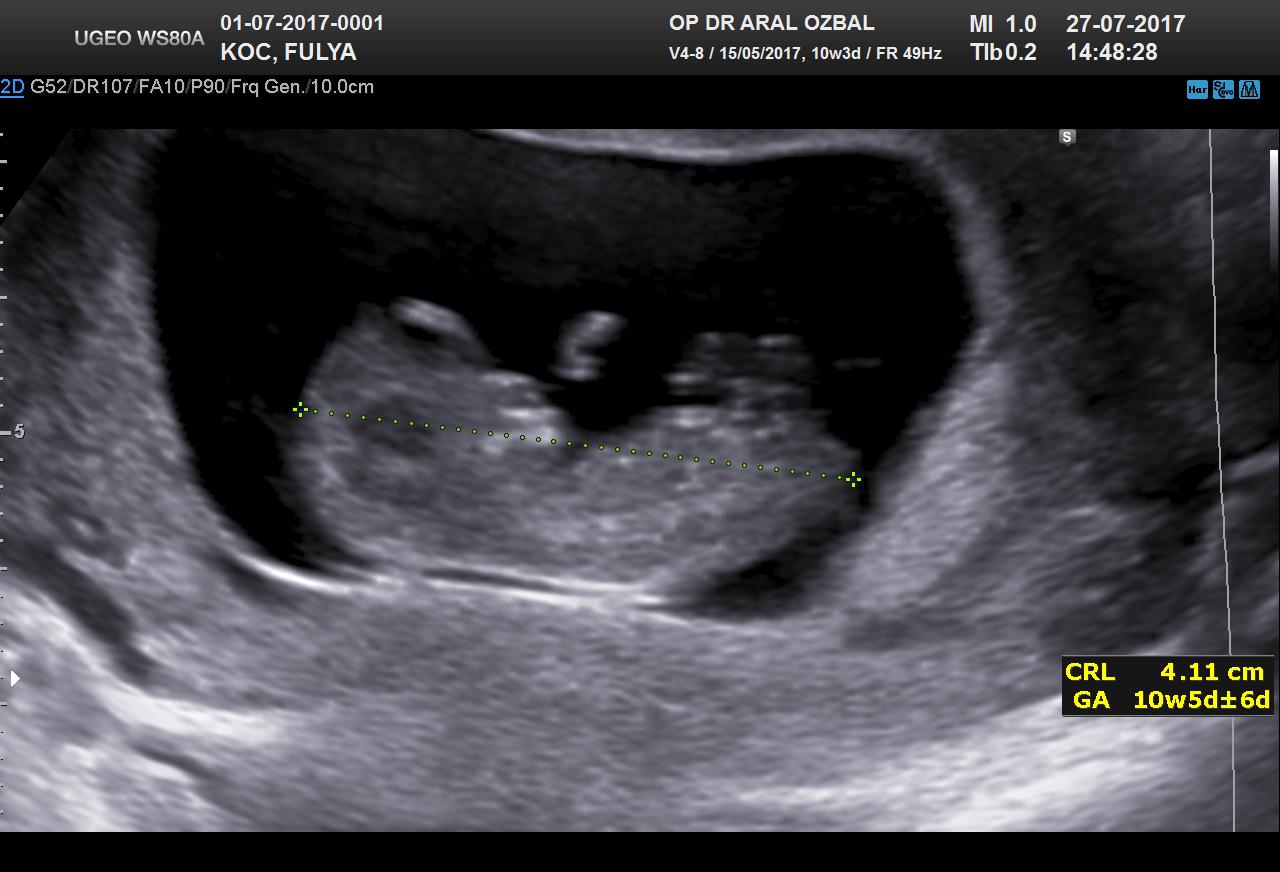

B Baharr@86 Forum Okuru 14 Ağustos 2017 #27 Benimkinede bakabilirmisiniz. 12+3 haftalık Ekli dosyalar 20170810111903_967.jpg 94,5 KB · Görüntüleme: 946 20170810111903_390.jpg 69,9 KB · Görüntüleme: 927

Uzman SühaN Administrator 14 Ağustos 2017 #28 Merhaba nub teorisine göre bebeğin poziyonu yan olmalı . Uygun görsele sahip değilsiniz bu yüzden değerlendirme yapamıyoruz.

Merhaba nub teorisine göre bebeğin poziyonu yan olmalı . Uygun görsele sahip değilsiniz bu yüzden değerlendirme yapamıyoruz.